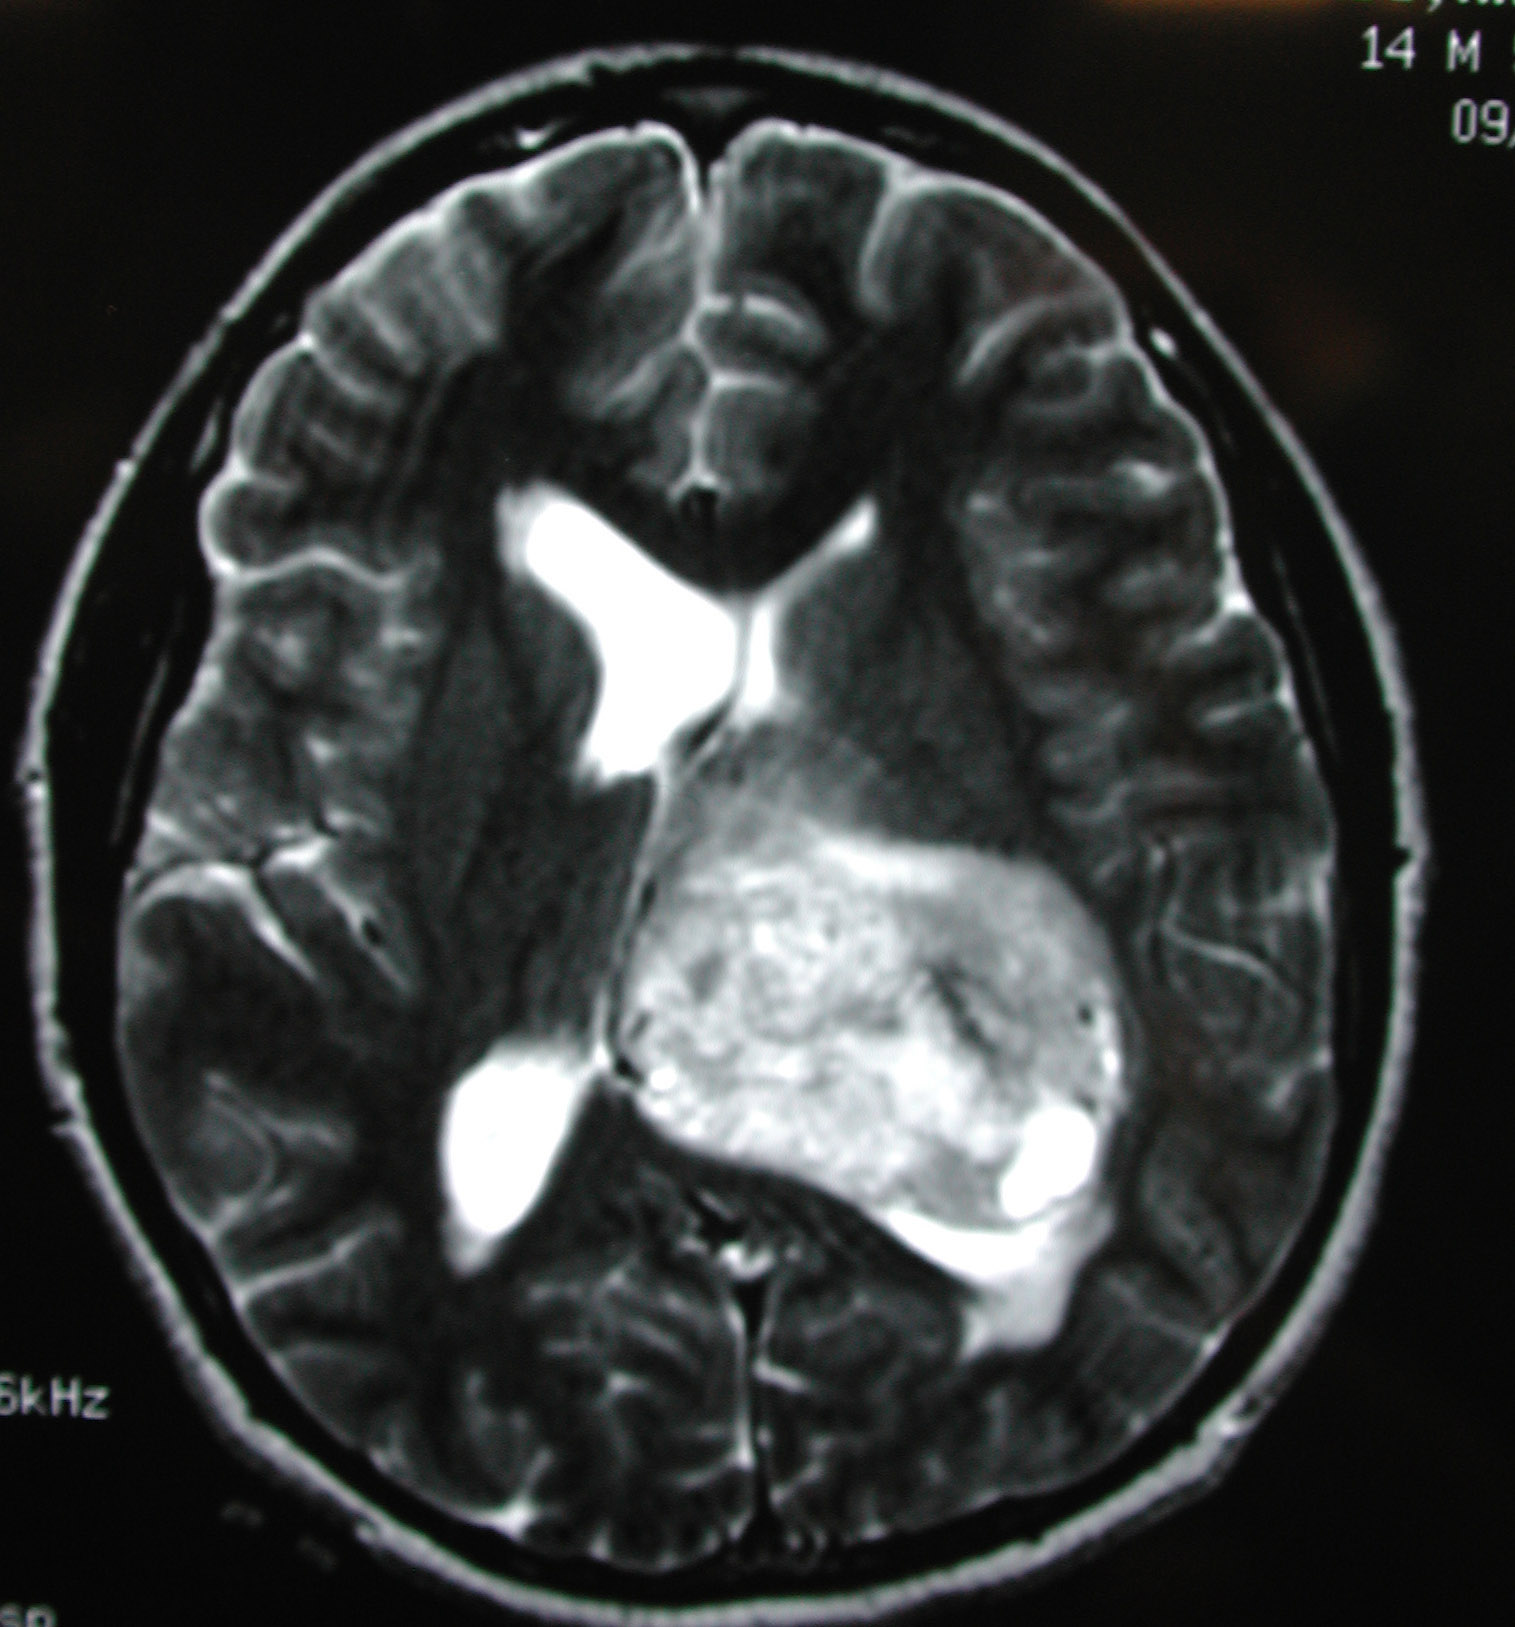

El análisis incluía a 1498 casos de tumores cerebrales malignos, con una edad media de 52 años. La mayoría del los pacientes (92%) estaban diagnosticados de gliomas y la mitad de los gliomas un 50,3% eran de la variedad más maligna, el astrocitoma grado IV (Glioblastoma multifome), con una supervivencia media de 18 meses desde su diagnóstico a pesar del tratamiento quirúrgico y con radioterapia y quimioterapia. Para comparar con los casos fueron incluidos en el estudio 3530 controles con una edad media de 54 años.

Se llega a la clara conclusión de que hay un aumento en el riesgo de aparición de gliomas por el uso prolongado de teléfonos móviles e inhalámbricos ajustados por edad de diagnóstico, sexo y nivel socioeconómico. El riesgo se incrementaba considerablemente en aquellos que llevaban muchos años, más de 25, usando con frecuencia los teléfonos tanto móviles como inhalámbricos. Además los tumores son diagnosticados con más frecuencia en los lóbulos temporoparietales que son los más expuestos a las radiaciones.

Fuente de la imagen Medscape. RMN con gadolinio de glioblastoma multiforme de alto grado de malignidad. Imagen cortesía de George Jallo. MD.